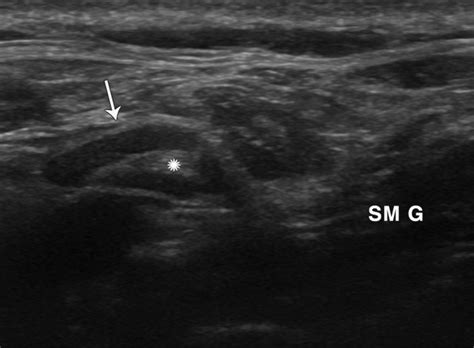

The visual and physical characteristics of these nodes often change significantly. They may feel hard, fixed, or conversely, fluctuant (soft/fluid-filled) if the necrosis has led to abscess formation. Imaging studies, such as CT scans or MRI, are the standard tools for identifying these nodes, as they show specific patterns of contrast enhancement that distinguish necrotic tissue from healthy or inflamed tissue.

CT/MRI Scan To identify the location and characterize the "ring enhancement" typical of necrotic nodes.

• Necrotic Lymph Node Ultrasound

• Necrotic Cervical Lymph Node